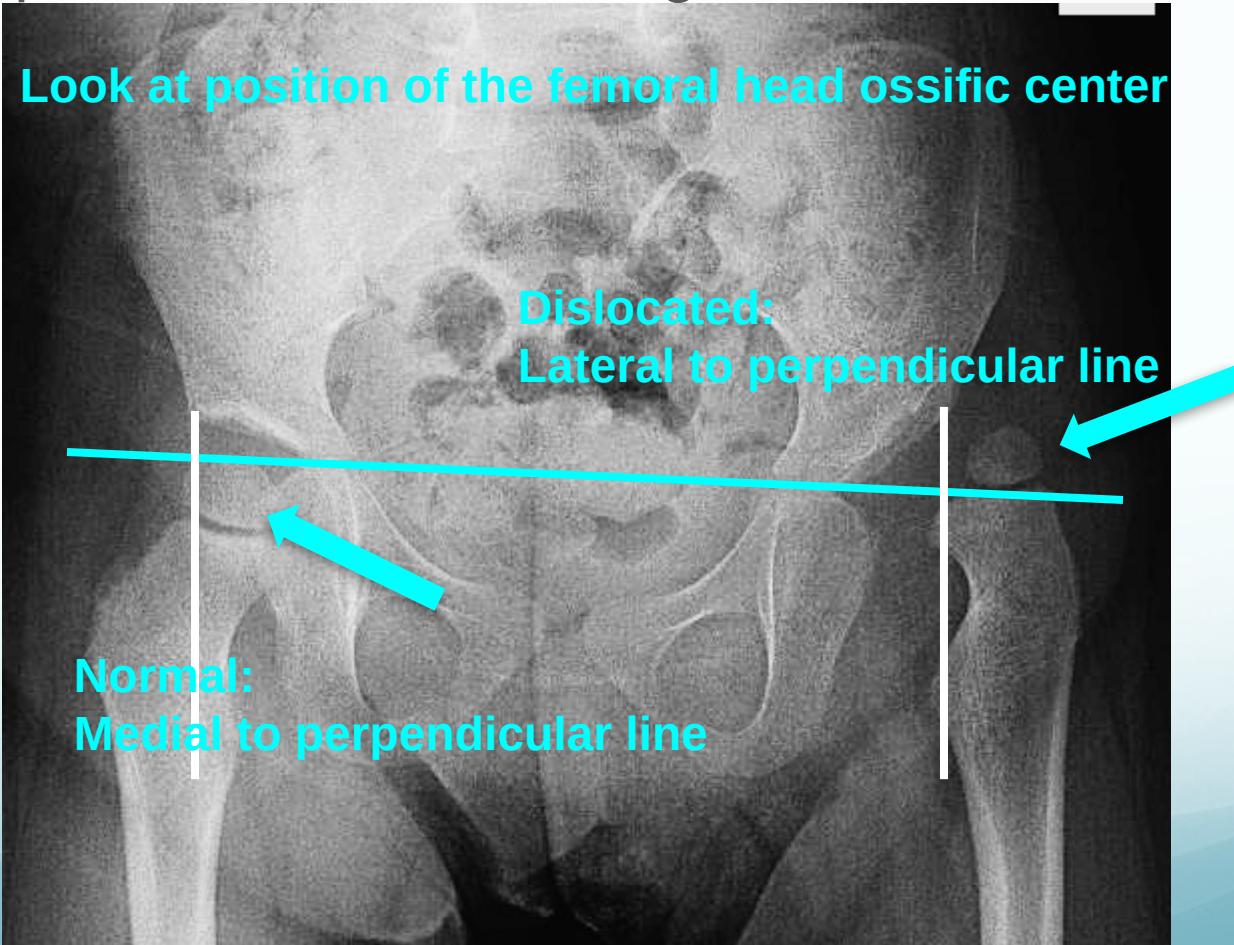

Position Assessment:

- Dislocated: Above the horizontal line

- Normal: Below the horizontal line

Perpendicular line from edge of acetabulum:

- Dislocated: Lateral to perpendicular line

- Normal: Medial to perpendicular line